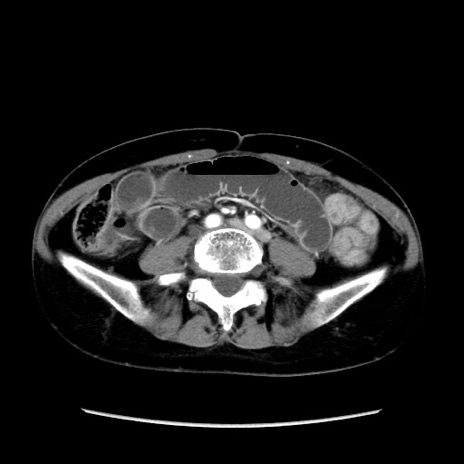

症例32(横断像)

【症例】40歳代 女性

【主訴】上腹部痛、嘔気・嘔吐

【現病歴】約9時間前頃から急に上腹部痛、嘔気、嘔吐が出現。改善しないため救急要請。

【既往歴】子宮頚癌(広汎子宮全摘術、放射線療法)、腸閉塞

【身体所見】腹部:平坦、軟、腸雑音亢進、上腹部を中心に腹部全体に圧痛あり。

【データ】WBC 8400、CRP 0.03